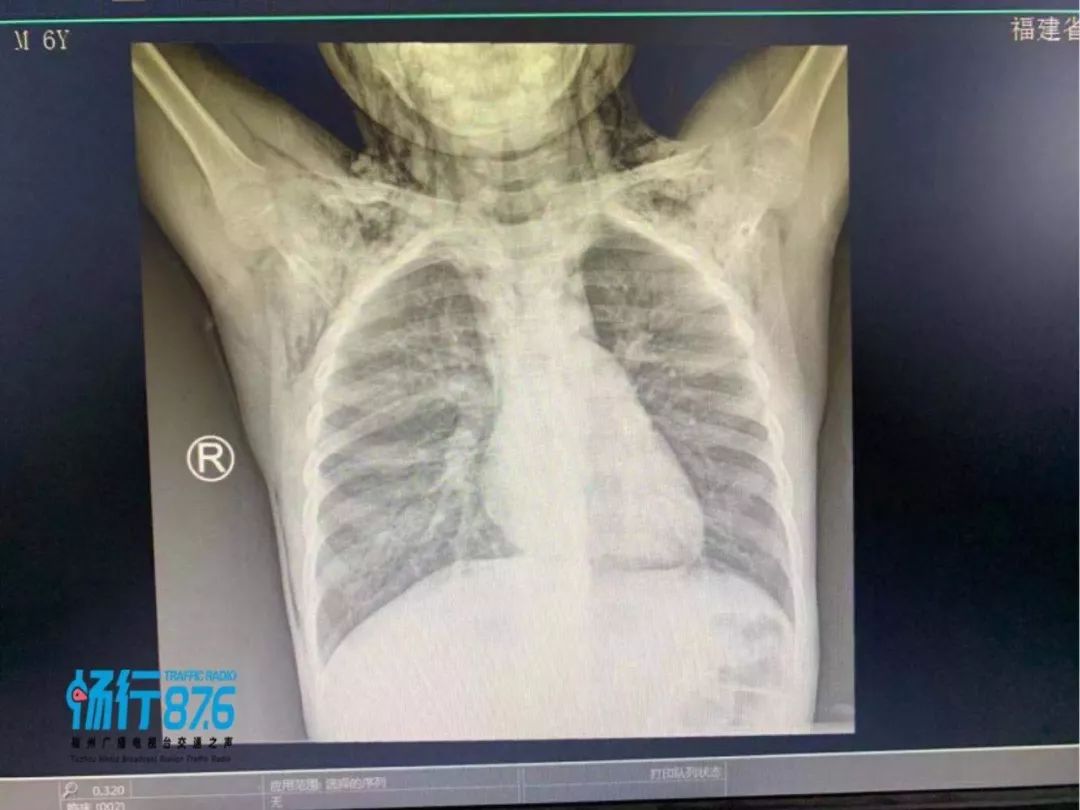

胸外科主治医师陈世恭医生告诉记者,“当时孩子送来面色苍白,剧烈咳嗽,精神状态较差,并且伴有气促,从孩子的颈部到胸壁腹壁皮肤有大量气泡,摸起来有握雪感,综合判断属于纵膈气肿这个疾病”。

医生所说的“纵隔气肿”是一种罕见的疾病,紧接着孩子被送进了监护室,通过吸氧、止痛、镇静、雾化、止咳、补液抗炎等对症治疗,经过和内科医生会诊,调整了治疗方案,期间复查复查颈胸CT及咽拭子病毒监测,提示颈部、纵隔、胸壁、上腹部皮下软组织多方积气、右肺炎症、双肺间质积气。

找到了原因,经过6天的治疗后,目前孩子颈部无疼痛,体温正常,咳嗽及气喘好转,一般情况良好,近日复查CT提示颈部及纵隔内气体大部分吸收,过几天康复后即可出院。